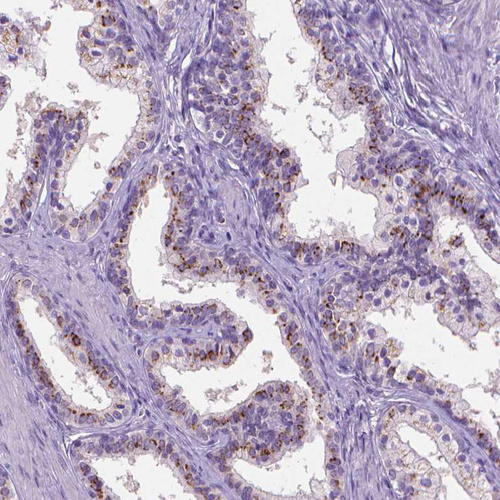

Immunohistochemistry analysis in human small intestine and skeletal muscle tissues using HPA064001 antibody. Corresponding SLC35C1 RNA-seq data are presented for the same tissues.